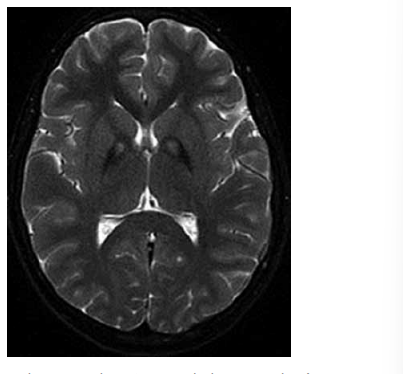

Menina de 4 anos de idade é trazida ao pronto-socorro por primeiro episódio de crise epiléptica e alteração do nível de consciência. Pais relatam que a criança iniciou há 3 dias diarreia com presença de sangue nas fezes e febre de 38ºC. Exames laboratoriais demonstram hemoglobina 7,8 g/dL, hematócrito 26%, plaquetas 32.000/mm³ e presença de múltiplos esquizócitos no esfregaço de sangue periférico. Creatinina 2,8 mg/dL, ureia 56 mg/dL, sódio sérico 135 mmol/L e glicemia 119 mg/dL.

O diagnóstico mais provável é: